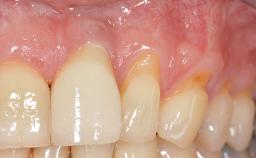

Implant Placement in the Esthetic Zone and Coverage of Multiple Gingival Recessions

This case illustrates use of a modified ‘tunnel’ technique, which has been shown to be highly effective in root coverage procedures. The tunnel technique is used to achieve soft-tissue augmentation across the anterior area, including the planned implant site, using collagen matrix as grafting material. The patient is a 47-year-old woman with high esthetic expectations. Her main concern was the appearance of the anterior teeth and their “elongation”.

Periodontal Phenotype Low-scalloped, thick Medium-scalloped, medium-thick High-scalloped, thin

Soft Tissue Anatomy Intact Defective

Soft Tissue Contour and Volume Significantly deficient